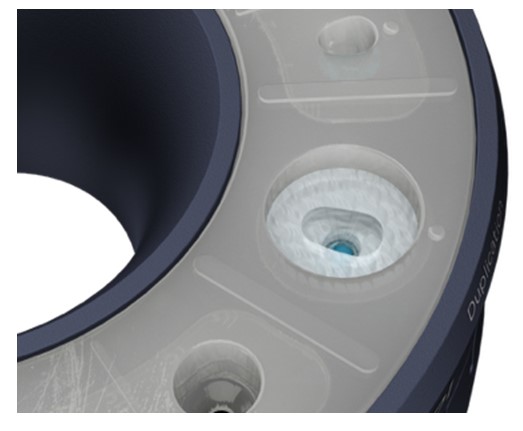

El / Ea introduce apoi materialul compozit adecvat în spațiul deschis și vindecă ușor cu unul sau mai multe trepte.

Apoi dezinstalează bontul personalizat de vindecare creat și continuă cu lustruirea suprafeței compozite și dezinfectarea corespunzătoare.

El / Ea introduce apoi materialul compozit adecvat în spațiul deschis și vindecă ușor cu unul sau mai multe trepte.

Apoi dezinstalează postul de imprimare duplicat creat și continuă cu lustruirea suprafeței compozite și dezinfectarea corespunzătoare.

Umple spațiul liber disponibil cu material compozit adecvat și fotopolimerizare într-unul sau mai multe trepte *.

Umple spațiul liber disponibil cu material compozit adecvat și fotopolimerizare într-unul sau mai multe trepte *.

Dezinstalează postarea de impresie duplicat generată din puțul de duplicare.